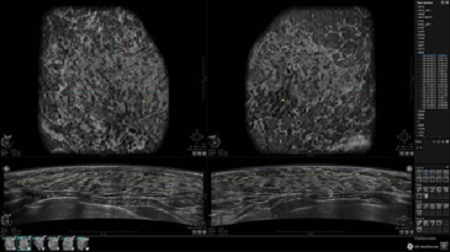

GE INVENIA ABUS – это современный УЗИ аппарат, который создан для точной и эффективной диагностики сканирования с высокой плотностью молочных желез. Выявляемость патологий раковых и предраковых стадий заболевания составляет 55%, что в конечном счете позволяет ставить врачу точные и своевременные диагнозы. Традиционные методы использования маммографии не показывают такой выявляемости, ограничиваясь лишь 3-38%.

УЗИ-аппарат GE INVENIA ABUS позволяет проводить максимально операторонезависимые процедуры, что значительно снижает риск неправильной постановки диагноза и сопутствующие издержки на обработку информации. Система готовит отчет в течение 3-х минут после сканирования, это безусловное преимущество по сравнению с обычным УЗИ сканером.

• Многооконный просмотр: 4 - 12 изображений

• Одновременный просмотр двух изображений для сопоставления в коронарной плоскости